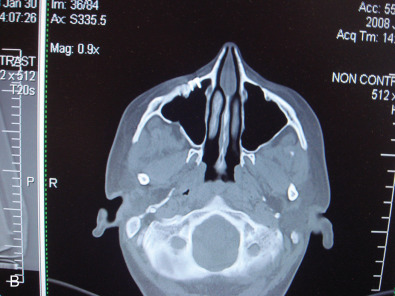

In obtaining the history from the patient, the most commonly overlooked source of posttraumatic facial pain is previous neurosurgery procedures , such as those for Chiari malformation ( Fig. 3.15.4A ), that require incisions at the base of the occiput, or those for brain tumor, such as acoustic neuroma, which are in the postauricular, mastoid area. Other less common causes related to neurosurgery are cerebrospinal shunt placements, burr holes, and the anterior site of tong placements. The next most frequently missed history point is a previous motor vehicle accident with a whiplash injury, which can cause pain related to the anterior scalene becoming adherent to the cervical and brachial plexus, or with an airbag inflation. Be sure to ask about childhood injuries to the craniofacial skeleton, such as a baseball ( Fig. 3.15.4B ) hitting the face, a fall from a bike, or other sports accidents, which must include heading a ball in soccer and concussion. Especially if the pain is related to V 2 or V 3 , inquire about dental surgery, particularly dental implants ( Fig. 3.15.4C ). Finally, when asking about previous facial surgery, ask directly about cosmetic surgery such as facelift ( Fig. 3.15.4D ), cheek implants, or jaw surgery, such as chin implant or orthognathic surgery.

While the computed tomography (CT) scans usually cannot demonstrate nerves directly, the injury to a bone adjacent to the known anatomical location of a nerve supports the diagnosis of posttraumatic facial pain due to that nerve. This is demonstrated in Fig. 3.15.5A where the left orbital floor is lower than it is on the right, and the infraorbital canal is deformed on the left. In Fig. 3.15.5B , the right infraorbital nerve is injured at the location of the fixation plate at the infraorbital rim. Another example is given in Fig. 3.15.6 , where the right inferior alveolar nerve was injured twice; the first time with a screw designed to hold a bone graft prior to dental implant placement, and then a second time, when a metal clip was placed on the mental nerve at the mental foramen. The application of 3T MRI to the cranial nerves has brought a new dimension to being able to evaluate posttraumatic facial pain and is the best way to document vascular compression of the trigeminal ganglia and its roots.